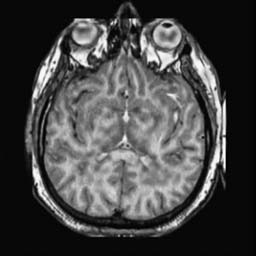

To demonstrate the effectiveness and efficiency of the proposed image fusion method , we conduct a set of comparative experiments on three image datasets. The first is composed by 8 pairs of multi-modal medical images and the second one contains 15 pairs of multi-focus gray or color natural images. These two datasets are often used in many related papers and some examples are shown in Figure 3(a) and Figure 3(b). The third one is a new multi-focus cervical cell image dataset collected by ourselves, which consists of 15 groups of color images and each group contains a series of multi-focus cervix cell images with size of or , etc. Some source examples are shown in Figure 3(c). Our source code implemented in C++ along with the new multi-focus cervical cell image dataset is available online.

We first evaluate the performance of the proposed method under varying total number of octaves and number of layers sampled per octave. The fused images of a pair of multi-modal medical images with different and are shown in Figure 4. In this example, on the one hand, when only 1 or 2 octaves are involved in constructing the DoG pyramid, the fused images fail to keep the integrity information of large size objects (e.g. eyeballs), while by increasing the value of , the integrity information of eyeballs is preserved. On the other hand, although not as significant as the increase of octave numbers , the fused image can contain more details by the increase of layer numbers . The corresponding objective quality metrics are shown in Figure 5. As shown in Figure 5(a), most of the metric values are improved as the number of octaves increases with the fixed layer numbers 3 in the global tendency and each of them tends to be stable when the number of octaves is 5. To get a relatively good quality from Figure 5(b), we can notice that some of the metric values can get a good performance when the number of layers is 3, such as the MI, SSIM, QI and VIF, though there are only a little change of all the metric values by increasing the number of layers with the fixed octave numbers 5. Because it will result in more computation burden with the increase of the value and , and for different kinds of source images, there are different performance with the diverse parameter settings. To get a trade-off between them in our experiments, we set for the multi-modal dataset, for the natural datasets and for the multi-focus cell dataset, respectively.

Figure 6 shows the fused images obtained by different methods with the multi-modal source images shown in Figure 3(a). As shown in these figures, the proposed method can produce images which preserve the complementary information of different source images well. Moreover, due to the scale-invariant structure saliency selection, our method can keep the integrity information of large size objects and the visual details simultaneously. Although the fused image generated by other methods can also capture the details to some extent, all of them fail to keep the integrity information of large size objects such as the eyeballs. Furthermore, from Figure 6(k)-6(t), the DTCWT, GFF, IM and NSCT methods may decrease the brightness and contrast while the proposed method can preserve these features and details without producing visible artifacts and brightness distortions.